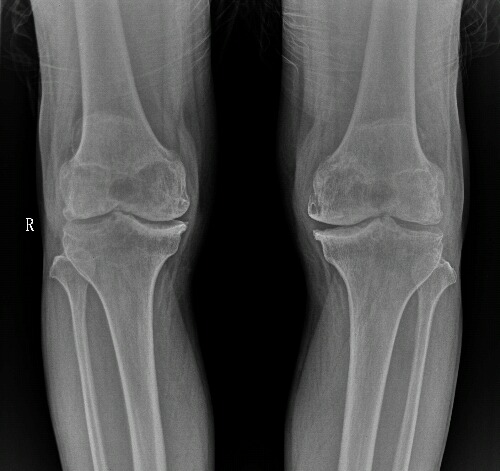

男,66.膝关节疼痛数月。滑膜软骨瘤?

双膝关节骨质增生硬化变尖,关节间隙狭窄,左关节囊内见多个结节,考虑双膝关节退变,左膝关节滑膜骨软骨瘤。

双侧膝关节退行性骨关节病伴左膝关节滑膜骨软骨瘤

双侧膝关节退行性骨关节病伴左膝关节滑膜骨软骨瘤病。